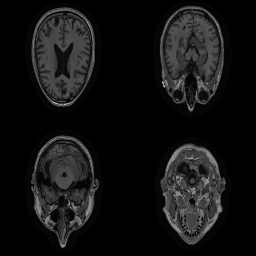

| Original | Renderings after de-identification | Original | MRI slices after de-identification | ||||||

|

![]() |

||||

| CP-GAN | FACE MASK | DEFACE | QUICKSHEAR | CP-GAN | FACE MASK | DEFACE | QUICKSHEAR | ||

Benchmark De-Identification Methods. We compare our result with three publicly available and widely-established methods for de-identification of MRI head scans, depicted in Figure 3. All methods have in common that they (1) are not deep-learning-driven, (2) require no additional training and (3), are used on a day-to-day basis in neuroscience and clinical research. All procedures were applied with default settings on images of resolution . The methods include QUICKSHEAR [Schimke et al.(2011)Schimke, Kuehler, and Hale], FACE MASK [Milchenko and Marcus(2013)], and DEFACE [Bischoff-Grethe et al.(2007)Bischoff-Grethe, Ozyurt, Busa, Quinn, Fennema-Notestine, Clark, Morris, Bondi, Jernigan, Dale, Brown, and Fischl]. Descriptions of the methods are provided in the Appendix. We also include MRI WATERSHED [Ségonne et al.(2004)Ségonne, Dale, Busa, Glessner, Salat, Hahn, and Fischl], a skull-stripping method that removes everything except the brain.